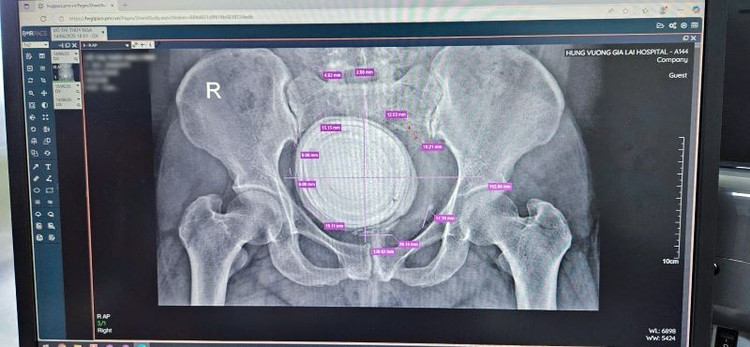

Viên sỏi bàng quang "khổng lồ" trên phim chụp - Ảnh BVCC

Qua thăm khám và thực hiện các cận lâm sàng, các bác sĩ phát hiện trong bàng quang bệnh nhân có một viên sỏi lớn chiếm toàn bộ lòng bàng quang, gây nguy cơ tổn thương niêm mạc, nhiễm khuẩn và suy giảm chức năng tiểu tiện.

Nhờ sự phối hợp nhịp nhàng và chuyên môn vững vàng, ê-kíp phẫu thuật đã lấy thành công viên sỏi có kích thước hơn 10cm, mang lại sự nhẹ nhõm sau nhiều năm đau đớn cho bệnh nhân.